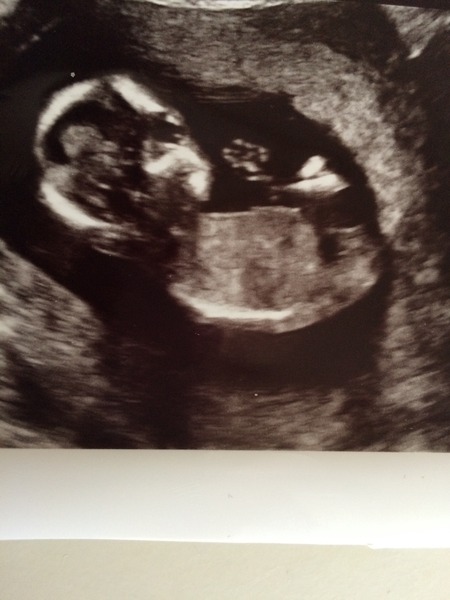

Could anyone tell me wot they think from my 14 week scan x